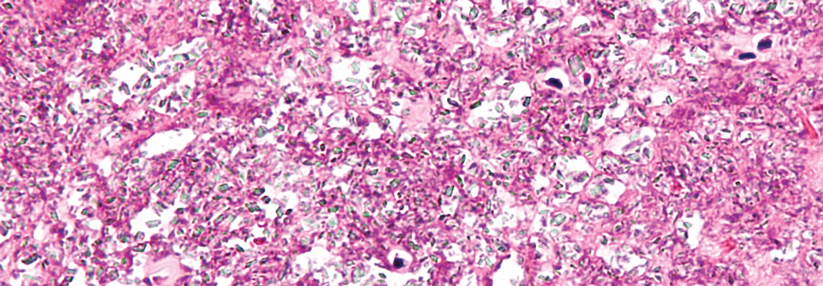

Im Gegensatz zu Kalziumpyrophosphat bildet Urat nadelförmige Kristalle. Im Gegensatz zu Kalziumpyrophosphat bildet Urat nadelförmige Kristalle. © iStock/toeytoey2530

Um welche der beiden Krankheiten es sich handelt, lässt sich mikroskopisch anhand der Gelenkflüssigkeit unterscheiden (siehe Kasten). Kann man nicht punktieren, lassen sich die eindeutigen Veränderungen je…